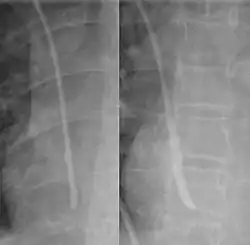

One form of thrombosis is the formation of a fibrin sheath around the catheter, and is one of the most common causes of catheter obstruction.[21] It is indirectly seen in these images before and after radiocontrast infusion, as the radiocontrast collects around the catheter.

Venous catheters may occasionally become occluded by kinks in the catheter, backwash of blood into the catheter leading to thrombosis, or infusion of insoluble materials that form precipitates. However, thrombosis is the most common cause of central line occlusion, occurring in up to 25% of catheters.[3]